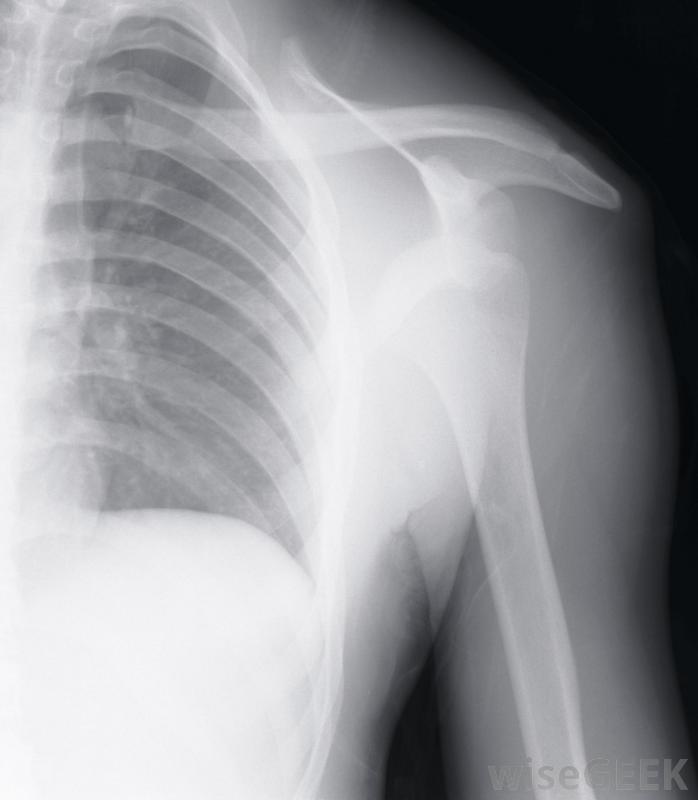

在进行肩峰成形术之前,外科医生可能需要做X光透视来观察肩关节的骨骼。运动员如果参加包括手臂和肩部头顶运动的体育活动,可能会患上撞击综合征如果肩关节疼痛,尤其是肩关节过度疼痛时,医生也可以用这种药物来缓解

如果患者出现持续性肩痛,他的外科医生可能想做一个肩峰成形术,他可能会先安排一系列的x光片来观察肩关节的骨骼。其他的检查,如核磁共振成像(MRI),也可能会被要求提供肩部有液体如果外科医生认为肩峰成形术对患者有利,则可将其作为开放手术或关节镜手术进行。